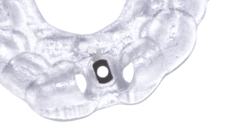

Given the significant buccal defect, guided bone regeneration (GBR) was performed simultaneously. A mixture of autologous bone and creos™ xenogain™ was applied to the defect and covered with a resorbable creos™ membrane to restore ridge width and support the buccal contour. In addition, a connective tissue graft was harvested and placed in the vestibular region to increase the thickness of keratinized mucosa. This combined approach addressed both hard and soft tissue deficiencies, providing the biological foundation for a stable and esthetic outcome.